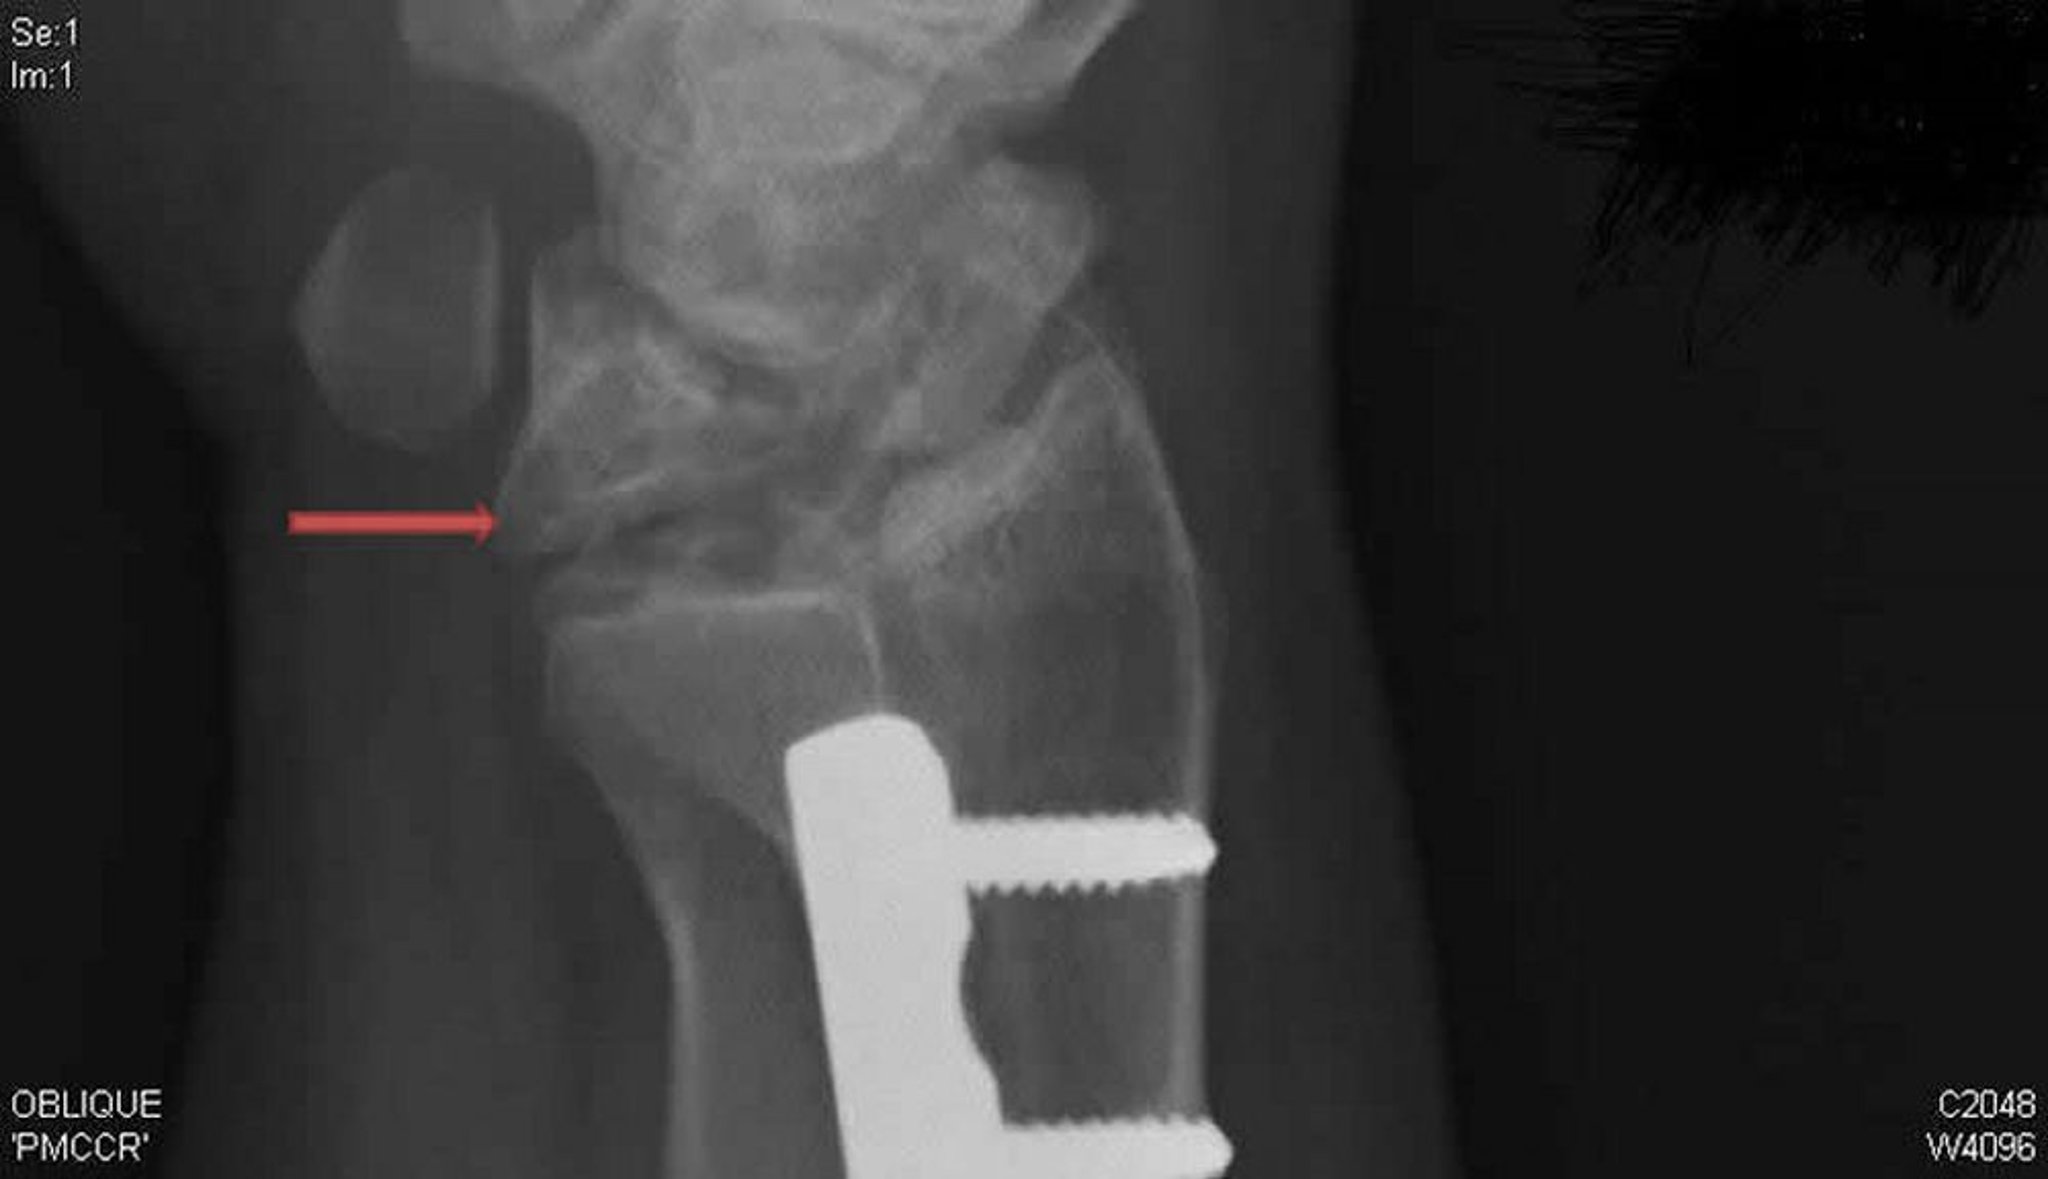

キーンベック病(X線斜位像)

右手関節を写したこのX線斜位像には,キーンベック病が示されている。後前像では明確でなかった月状骨の圧潰および断片化(矢印)に注目すること。

Radiograph courtesy of David R.Steinberg, MD.